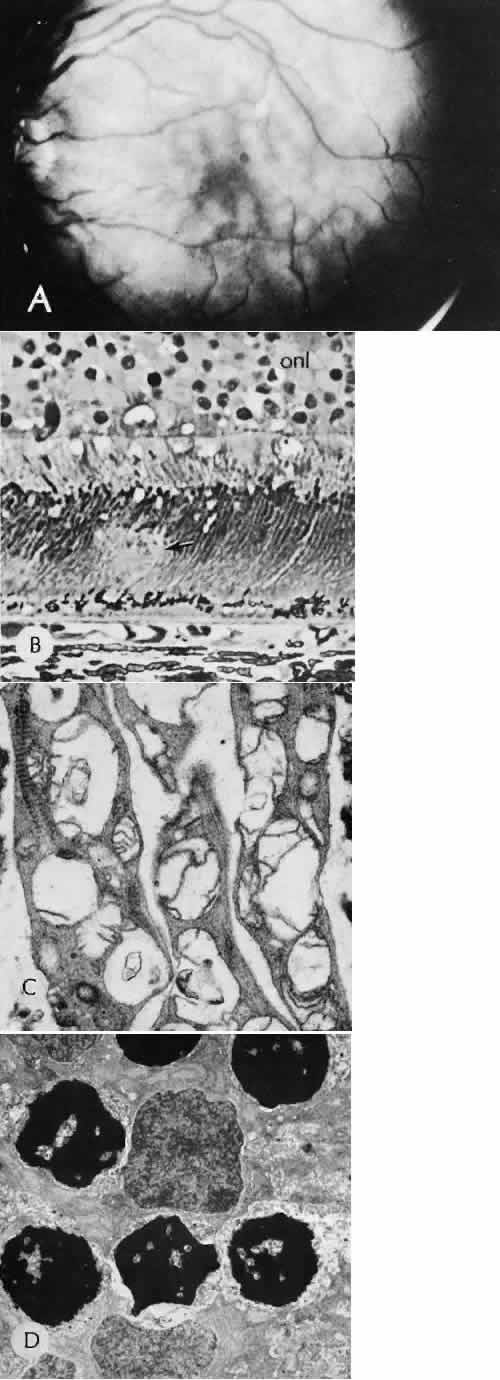

RETINAL HEALING

Wound healing of the neurosensory retina follows the principles of wound healing. There is an initial removal of all necrotic tissue by phagocytosis followed by proliferation of cells to form a chorioretinal bond. The healing, however, is modified in most instances by the lack of participation by the blood vessels.43–45 Astrocytes from the neurosensory retinaproliferate from the peripheral viable tissue into the wound and downward into the area of the subretinal space (Fig. 12). Retinal pigment epithelial cells from the peripheral viable tissue undergo fibrous metaplasia and proliferate upward into the area of the subretinal space. When the two proliferating cell types unite, a tight chorioretinal bond is formed. Increased retinal adhesiveness has been estimated to be 140% of the normal degree of adhesiveness 2 weeks after photocoagulation.46 Retinal holes may heal spontaneously if supported by an intact vitreous base or if located adjacent to the retinal pigment epithelium (Fig. 13).47,48 For the retinal pigment epithelium to differentiate, it must be in contact with overlying retinal pigment epithelium.49 Choriocapillaris repair from a photocoagulation wound of the retina appears to proceed in a manner similar to that of repair of capillary thrombosis in other tissues.50 The vascular repair process may not reproduce the lobular architecture of the native choriocapillaris.51 The choriocapillaris may regenerate in areas of restored retinal pigment epithelium.52 Proliferative vitreoretinopathy is an expression of abnormal retinal wound healing.53

Fig. 12. Light micrograph of an area over a retinal buckling element for retinal reattachment. Cryotherapy has been applied in the area, causing atrophy of the neurosensory elements of the retina. There is an intimate association of the remaining glial elements of the retina (R) with proliferated retinal pigment epithelial cells in the plane of the former subretinal space (arrow). The adhesion prevents intraretinal separation in this area. (Periodic acid-Schiff stain; × 100.)

Fig. 13. Retinal healing by proliferation of glial cells. In the presence of an intact vitreoretinal interface acting as a scaffolding, retinal glial cells are able to proliferate and seal small retinal holes. The arrow indicates artifactually detached vitreoretinal interface.

Interruption of Bruch's membrane may allow the ingrowth of fibrovascular tissue from the choroid into the subretinal space, resulting in a modified granulation wound healing process and subretinal scarring.54